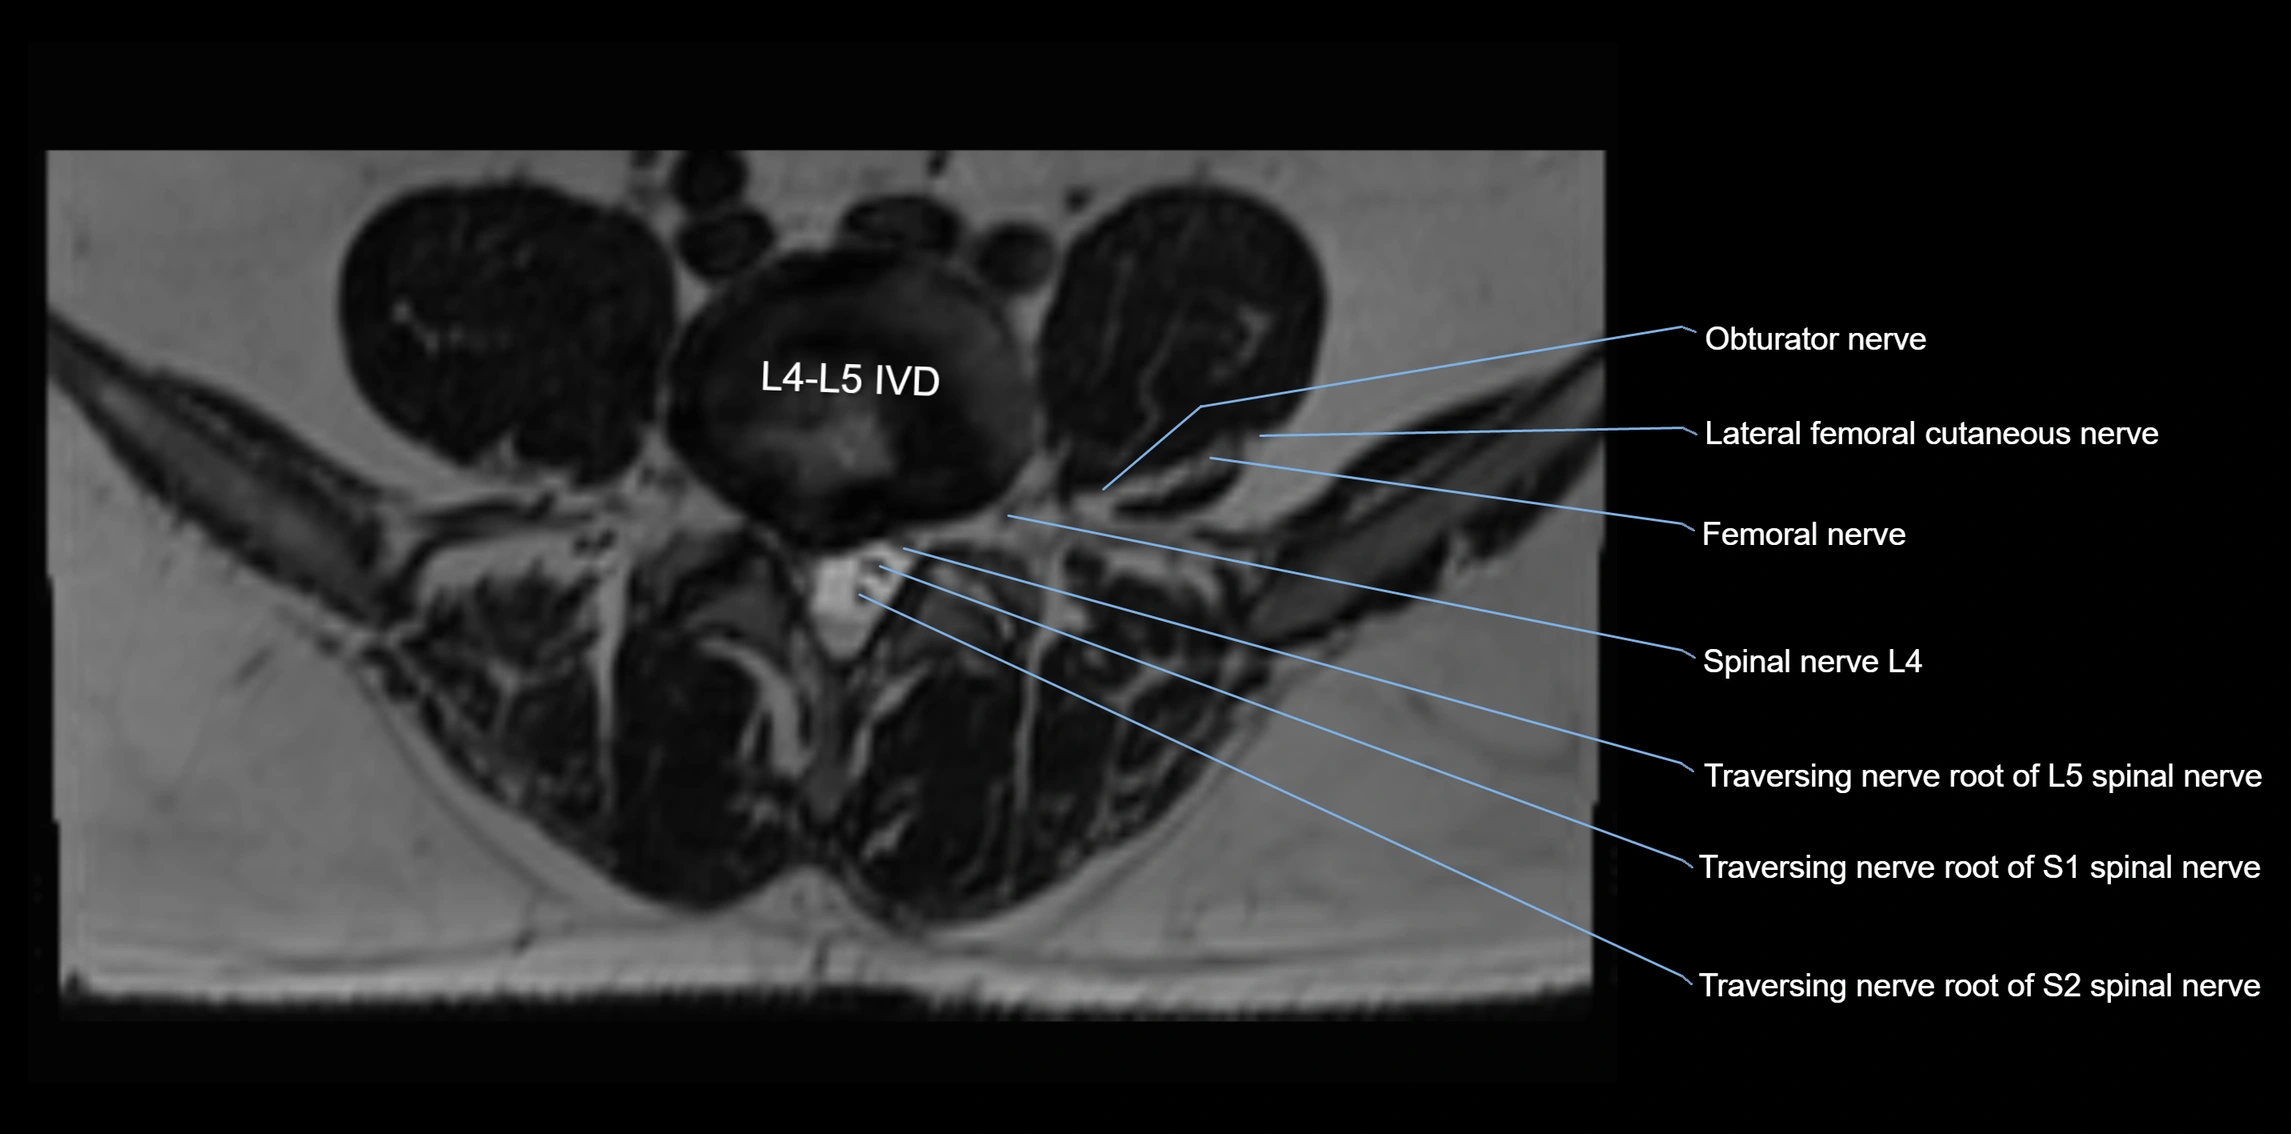

MRI image

image